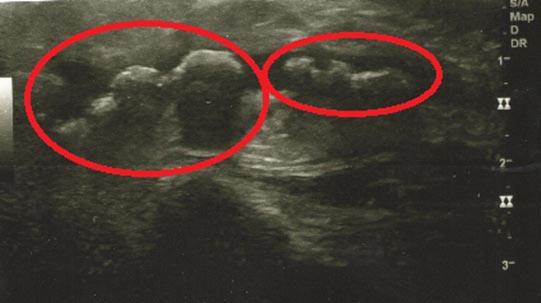

Результаты и их обсуждение. В результате применения сиалолитотрипсии фрагментация камней была достигнута у 36 из 39 пациентов (92,3%, р=0,0323). У 16 больных во время сиалолитотрипсии или сразу после 1-го сеанса произошла фрагментация конкремента, после 2-го сеанса — у 8 человек, после 3-го сеанса — у 6 пациентов, после 4-го — у 3, после 5-го — у 3 больных (рис. 2 и 3).

Рис. 3. Ультразвуковое исследование пациента с конкрементом в протоке околоушной слюнной железы после 2 сеансов сиалолитотрипсии